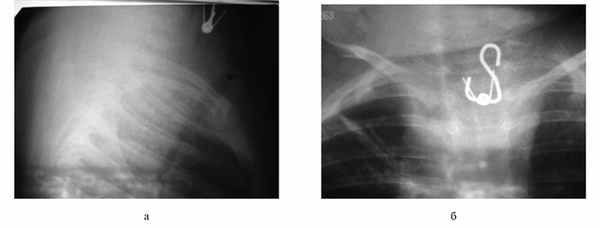

Второй случай длительного нахождения инородного тела в пищеводе у ребенка в возрасте 1 года обусловлен неправильной оценкой лечащими врачами клинических проявлений заболевания, а также данных, полученных при рентгенологическом обследовании органов грудной клетки.

Больной Я., 1 год, житель Курска, поступил в ЛОР-отделение 24.12.14 с диагнозом: инородное тело пищевода. Из анамнеза установлено, что ребенок заболел 09.12.14, когда у него появилась высокая температура, беспокойство, одышка; отказывался от приема пищи. Машиной скорой помощи доставлен в инфекционную больницу, где был поставлен диагноз: двусторонняя внебольничная пневмония, острый обструктивный бронхит, дыхательная недостаточность I—II степени. Лечение проводилось в реанимационном отделении, ребенок получал инванз, амикацин, максипин, ингаляции с беродуалом и амбробене, виферон. При поступлении была выполнена рентгенография органов грудной клетки, однако шейный отдел пищевода не был исследован. При внимательном осмотре рентгенограммы удалось заметить тень нижнего края инородного тела. 17.12.14 повторно была выполнена рентгенография органов грудной клетки, где на профильном снимке визуализируется инородное тело (крючок) металлической плотности (рис. 2, а, б), однако этот факт остался незамеченным лечащими врачами. Больной наблюдался до 24.12.14. В этот день его перевели в детскую областную больницу с диагнозом двусторонняя пневмония, острый бронхит, где сразу же была выполнена рентгенограмма органов грудной клетки, на которой четко выявилось инородное тело пищевода, и ребенок был срочно переведен в ЛОР-отделение. В этот же день в 18.00 ребенку под интубационным наркозом трубкой № 3 эзофагоскопа Мезрина произведена ригидная эзофагоскопия. Ниже входа в пищевод обнаружено инородное тело, оказавшееся пластмассовой прищепкой, с помощью которой штора крепится к оконному карнизу (рис. 3). Прищепка удалена из пищевода вместе с трубкой эзофагоскопа. Сразу же после удаления произведена фиброскопия пищевода, на боковой стенке справа обнаружен фибринозный налет на участке размером около 1 см. В 20.30 произведена рентгенография пищевода с контрастом (урографин), затека контрастного вещества в средостение не выявлено. На следующий день ребенок переведен в удовлетворительном состоянии в детскую областную больницу, откуда выписан по выздоровлении 29.12.14.

Рис. 2. Рентгенограмма органов грудной клетки больного Я. от 17.12.14 (а) и от 24.12.14 (б).

Рис. 3. Инородное тело пищевода (прищепка для штор).